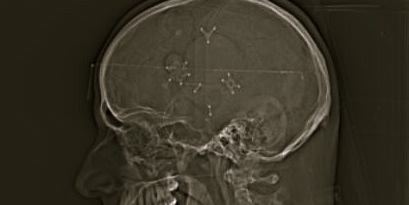

I underwent surgery for a fractured skull. Actually, there were two fractures: one above my right eye, and the other along the right side of my head, most likely caused by my brain hitting the inside of my skull after the car came to an abrupt stop. It was under that part of my skull that a clot, an epidural hematoma, had to be removed. My head was then closed with some metal plates and 42 staples.

Recently, I’ve felt some pain near one of the bumps near my right temple — a sort of sharp twinge, and definitely noticeable. I sought out the original neurosurgeon — the one and only person who actually saw and touched my brain — for some answers. He explained that it was common for things to shift, but to be on the safe side, I should undergo some tests. Here is a close-up.

Despite what many people think, I clearly do not have flowers on the brain. Although the surgeon said there was no cause for alarm, I needed a diagnosis. So, I gave myself one. In laymen’s terms, I have a screw loose.

Hi Ann. The funny part is is that it never occurred to me that there was metal in my head — but then I saw the x-ray. Of course, it makes perfect sense. The proof is in the photo: I’m clear-headed. 🙂